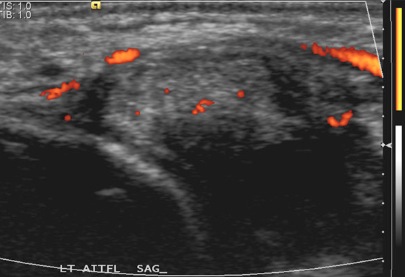

Figure 2 for case AITFL Desmitis

Figure 2

39 with on-going anterolateral ankle pain 9 months after syndesmosis injury. Pain, tenderness and swelling all localised to the AITFL. US shows AITFL Desmitis with tender, diffusely swollen and mildly hyperaemic ligament (arrows).

AITFL Desmitis